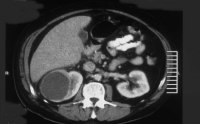

Diagnose und Behandlung von komplexen renalen Zysten bzw. unklaren Befunden umfassen eine Kombination von Sonographie, Urographie und CT (Abbildung 1). Dadurch soll eine Abgrenzung zwischen gutartigen und bösartigen Veränderungen erfolgen.

Die Abklärung bei komplexen zystischen Prozessen ist im Algorithmus aufgezeigt (Abbildung 2).